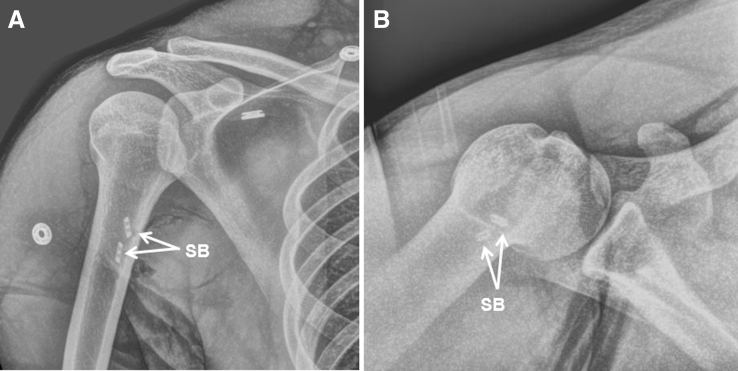

After irrigation, closure of the wound is performed in layers with buried interrupted absorbable suture for the deep dermal layer and a running subcuticular absorbable suture for the skin. A sterile dressing is applied, and the patient is placed in a sling. Postoperative radiographs are obtained to visualize the suture buttons abutting the cortex (Fig 7).

Fig 7.

Postoperative radiographs of the right shoulder of a baseball pitcher status after right latissimus tendon repair as shown in this case. Anteroposterior (A) and axillary lateral (B) views show 2 suture buttons appropriately placed and engaging the humeral cortex. (SB, suture button.)